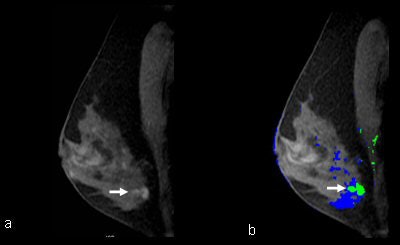

| MR images, without and with CAD, applied in a 50-year-old patient with a strong family history of breast cancer with a left breast MRI-detected benign lesion, diagnosed at MRI-guided vacuum assisted biopsy. (a) Sagittal T1-weighted 2D spoiled gradient recalled (SPGR) fat-suppressed (150/4.2; flip angle, 50°; matrix, 256 x 128; field-of-view 20 cm; slice thickness, 3 mm) image shows clumped linear enhancement (arrow) in the central left breast. (b) CAD assessment of the lesion demonstrated enhancement at all the threshold levels. At 80% threshold (arrow) CAD color mapping of the delayed enhancement pattern shows predominantly blue with some green, indicating a persistent delayed enhancement pattern that did not differ from the remaining background enhancement. This was therefore assessed as benign based on CAD. All images courtesy of Dr. Tal Arazi-Kleinman, Sunnybrook Health Sciences Centre. |